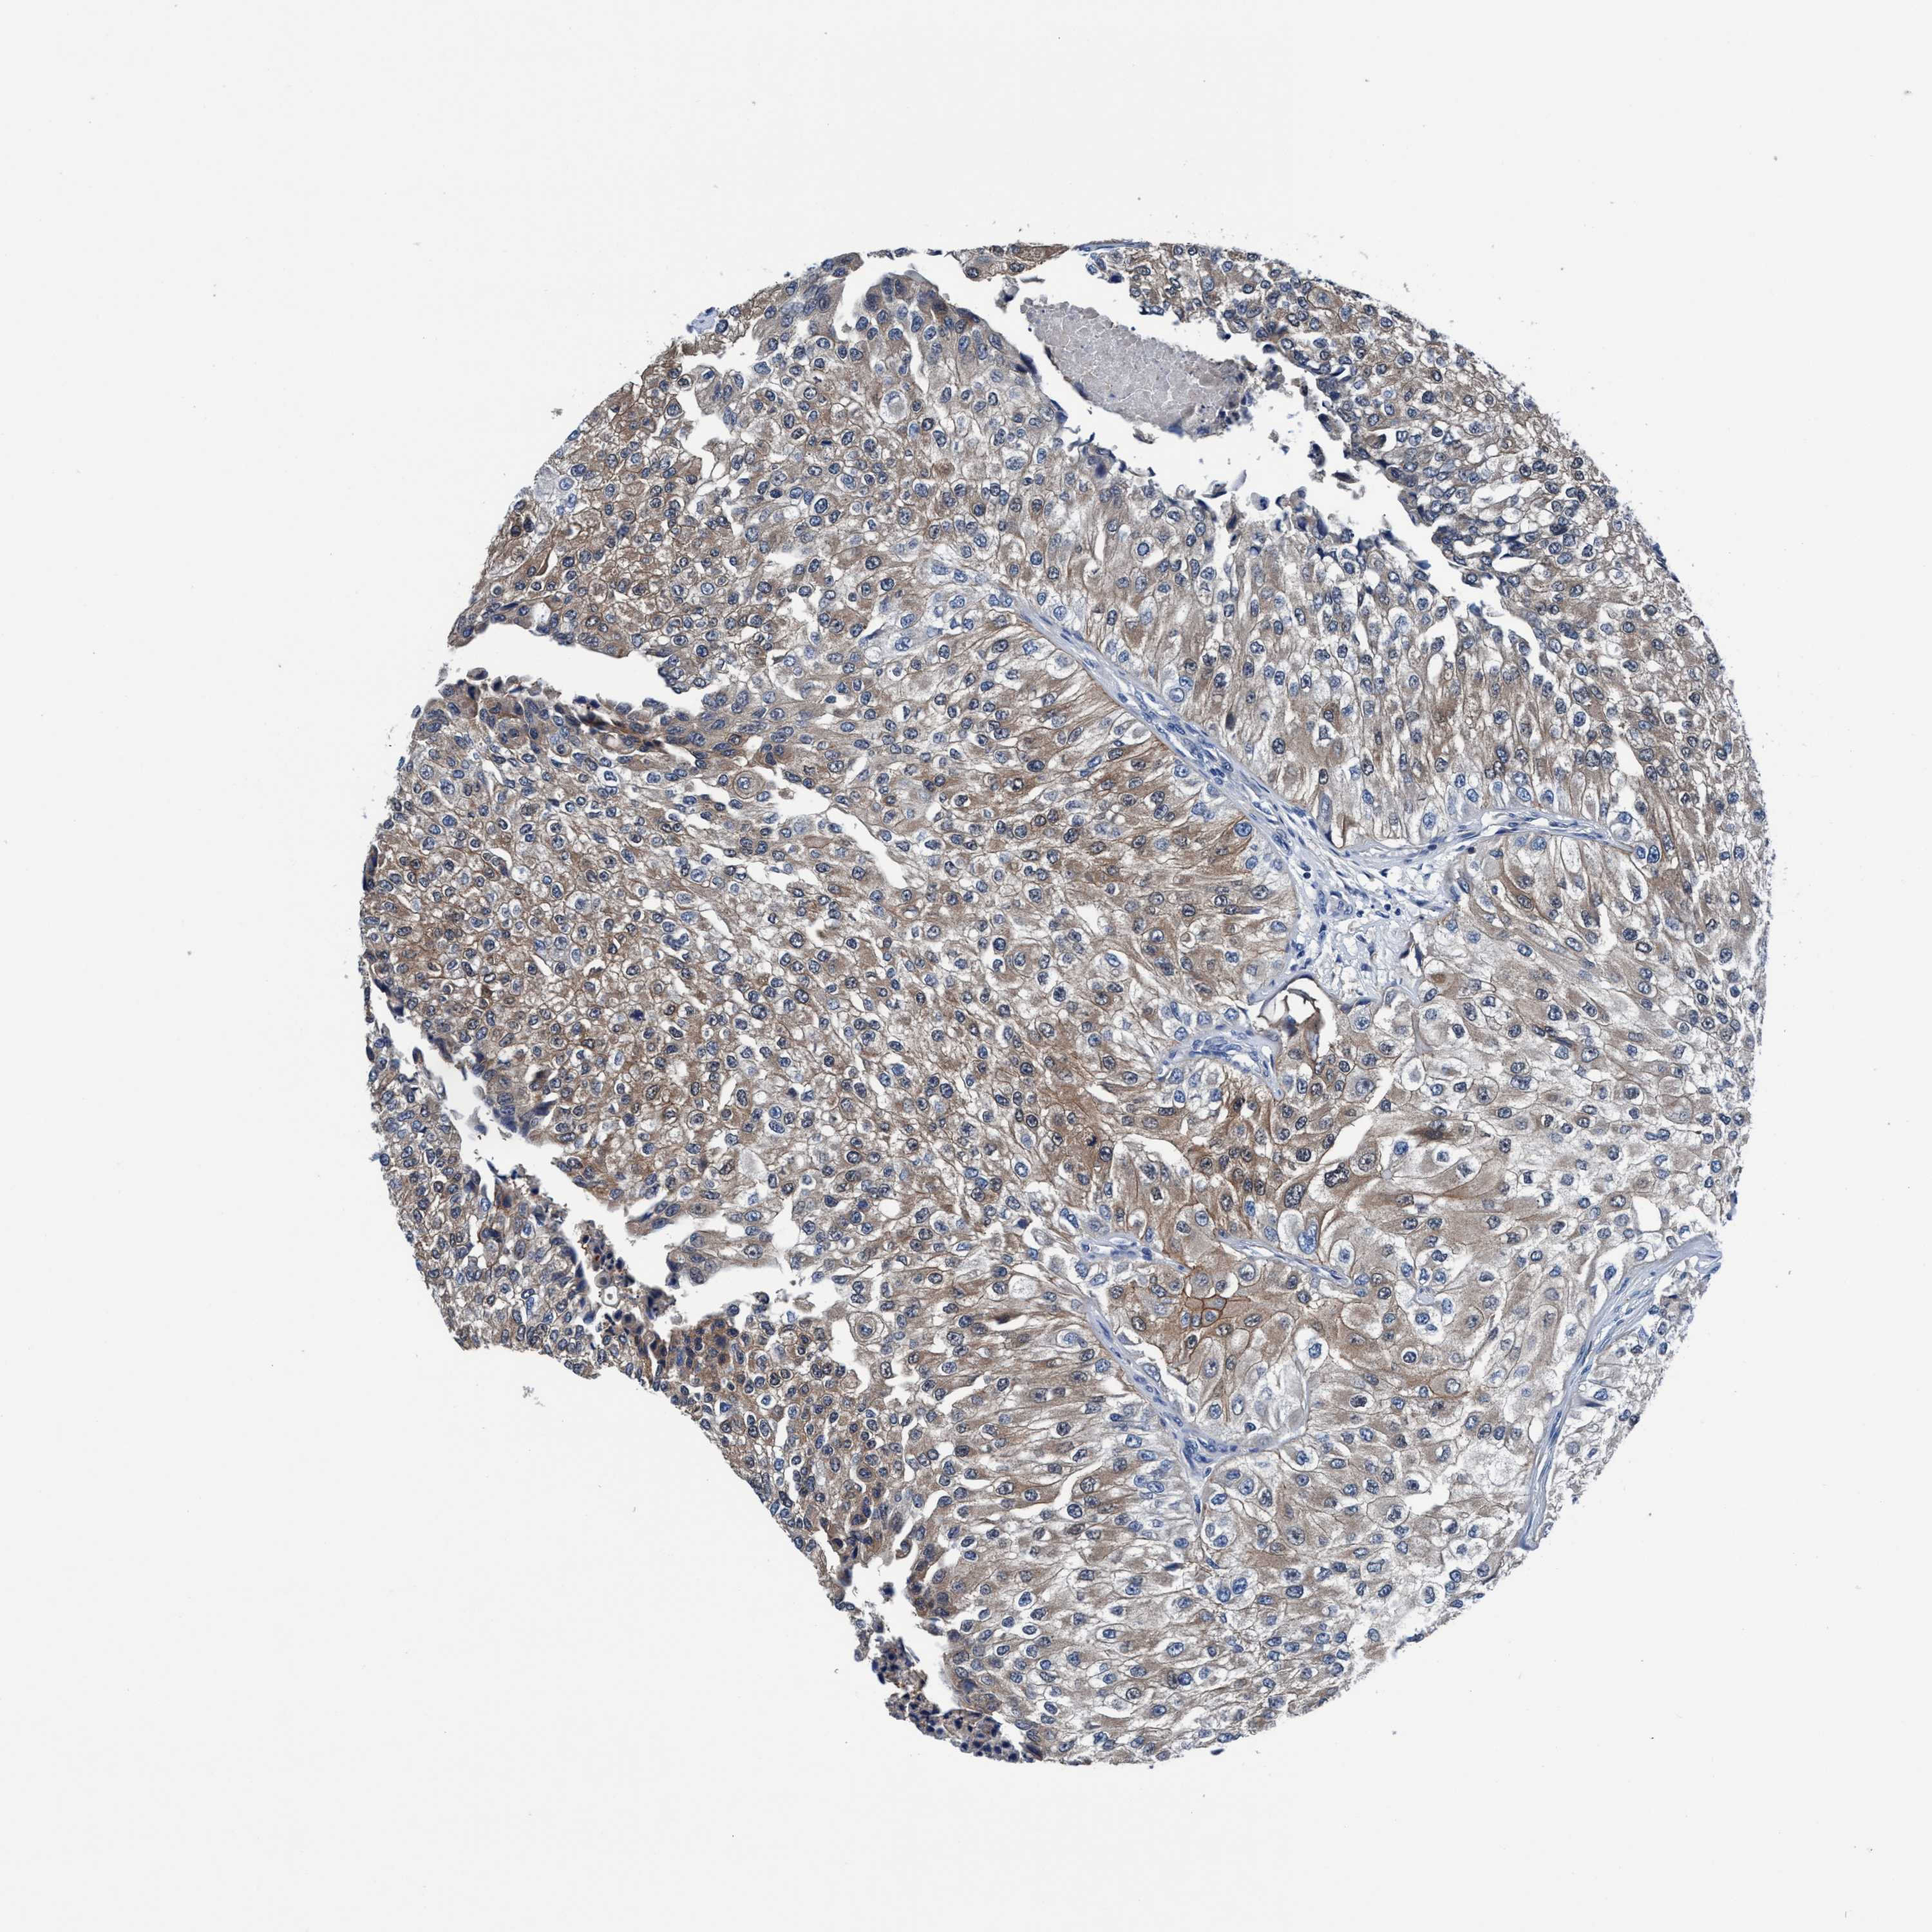

UROTHELIAL CANCER - Protein expressioni

A mouse-over function shows sample information and annotation data. Click on an image to view it in a full screen mode. Samples can be filtered based on level of antibody staining by selecting one or several of the following categories: high, medium, low and not detected. The assay and annotation is described here.

Note that samples used for immunohistochemistry by the Human Protein Atlas do not correspond to samples in the TCGA dataset.

Antibody stainingi

Antibody staining in the annotated cell types in the current human tissue is reported as not detected, low, medium, or high, based on conventional immunohistochemistry profiling in selected tissues. This score is based on the combination of the staining intensity and fraction of stained cells.

Each image is clickable and will lead to virtual microscopy that enables deeper exploration of all samples and also displays staining intensity scores, fraction scores and subcellular localization as well as patient and tissue information for each sample.

Antibody HPA008423

Staining

High

Medium

Low

Not detected

Intensity

Strong

Moderate

Weak

Negative

Quantity

>75%

75%-25%

<25%

None

Location

Urothelial carcinoma, Low grade

Urothelial carcinoma, High grade